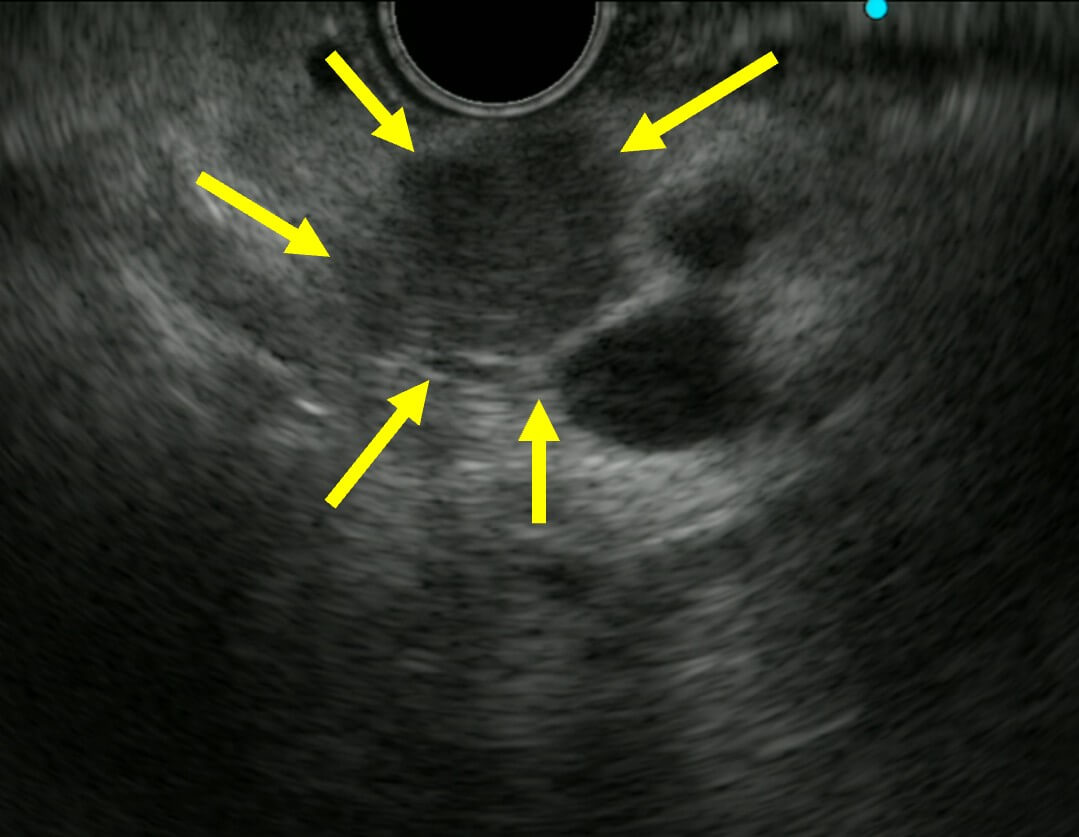

超音波内視鏡検査(EUS)

超音波内視鏡(EUS)は、膵癌の診断と管理において非常に重要な役割を果たしています。EUSは、内視鏡の先端に高解像度の超音波を搭載した装置で、口から挿入され、胃や十二指腸の壁に近接して膵臓を観察することができます。この近接観察により、CTやMRIでは発見が難しい小さな膵腫瘍を検出することが可能です